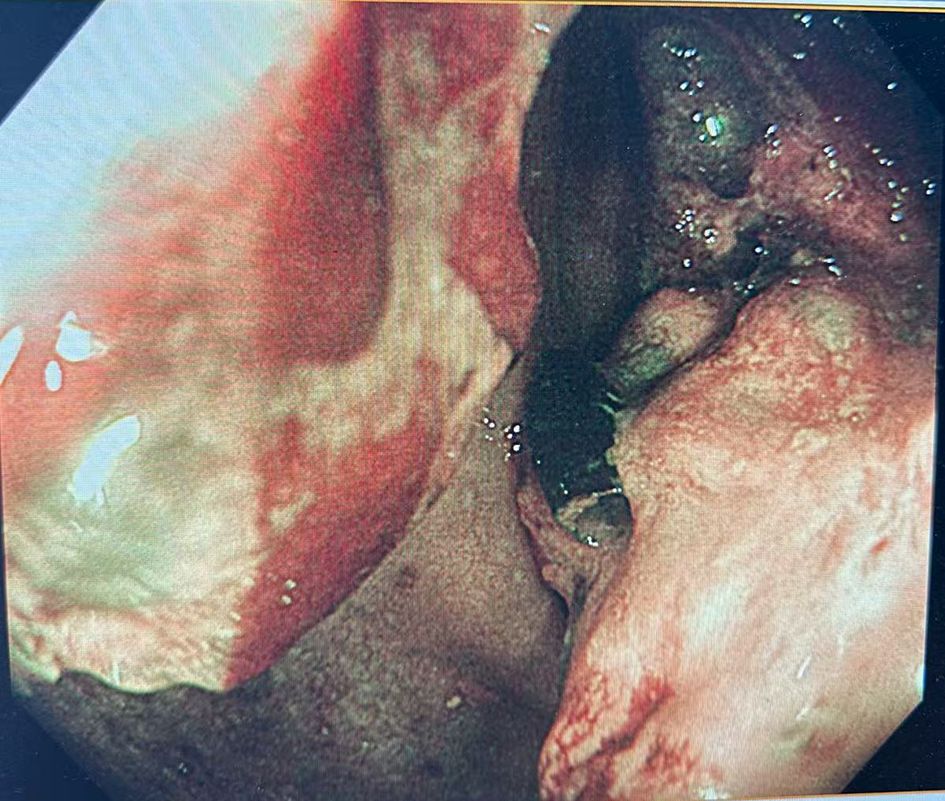

Colonoscopy demonstrated an ulcerative stricture in the ascending colon, and histopathological examination of the biopsy confirmed poorly differentiated adenocarcinoma (Figure 1). Imaging studies, including thoracoabdominal computed tomography (CT), revealed an ascending colon mass with mildly enlarged regional lymph nodes (Figure 2). The patient had no significant comorbidities, and preoperative cardiopulmonary evaluation confirmed suitability for surgery.

Figure 1. Colonoscopic showing an ulcerative stricture in the ascending colon.